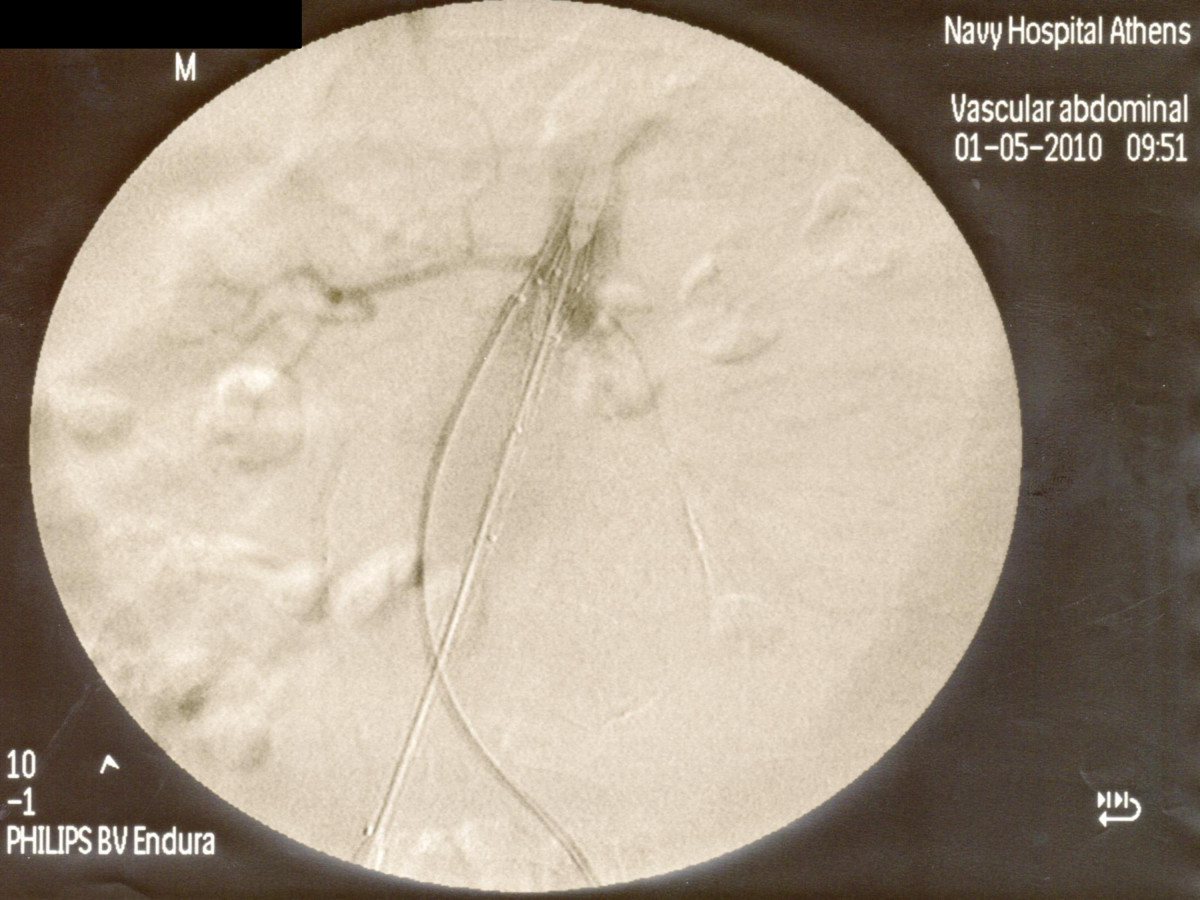

Ενδαγγειακή αποκατάσταση ανευρυσμάτων κοιλιακής αορτής

12ο Πανελλήνιο Συνέδριο Αγγειακής και Ενδαγγειακής Χειρουργικής

2010, Αθήνα